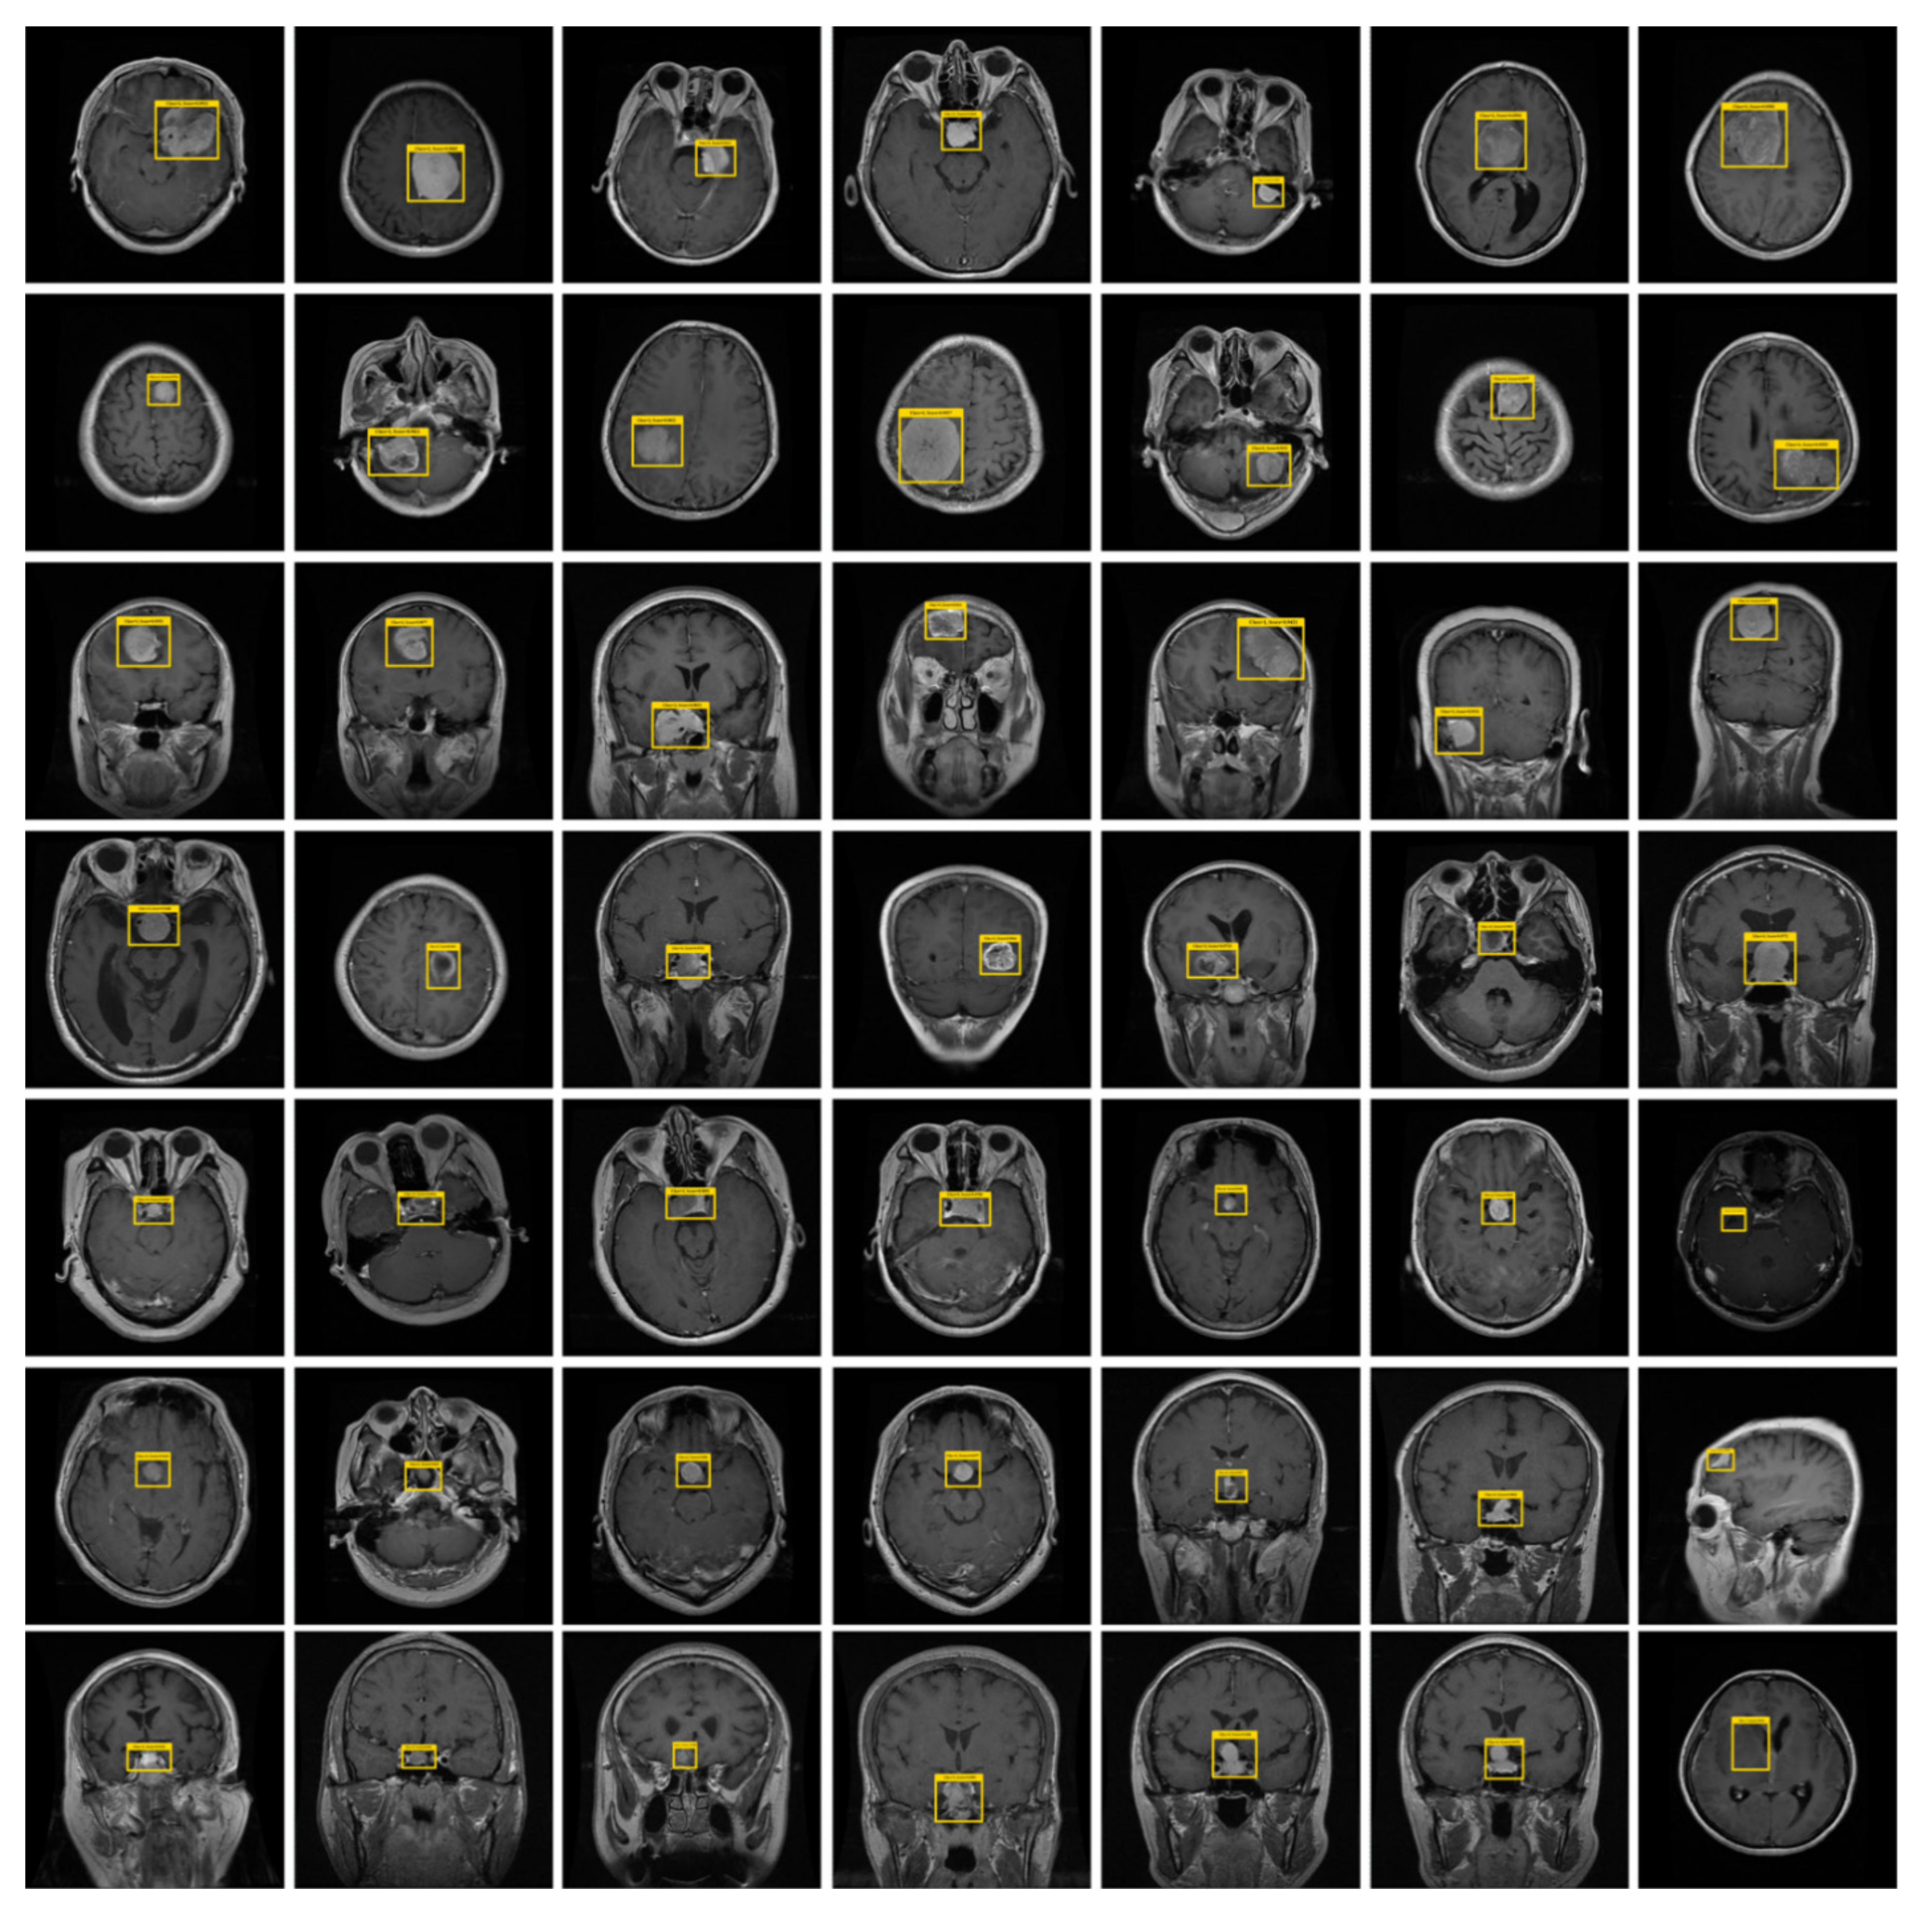

3.1. Annotations

4.1. Dataset